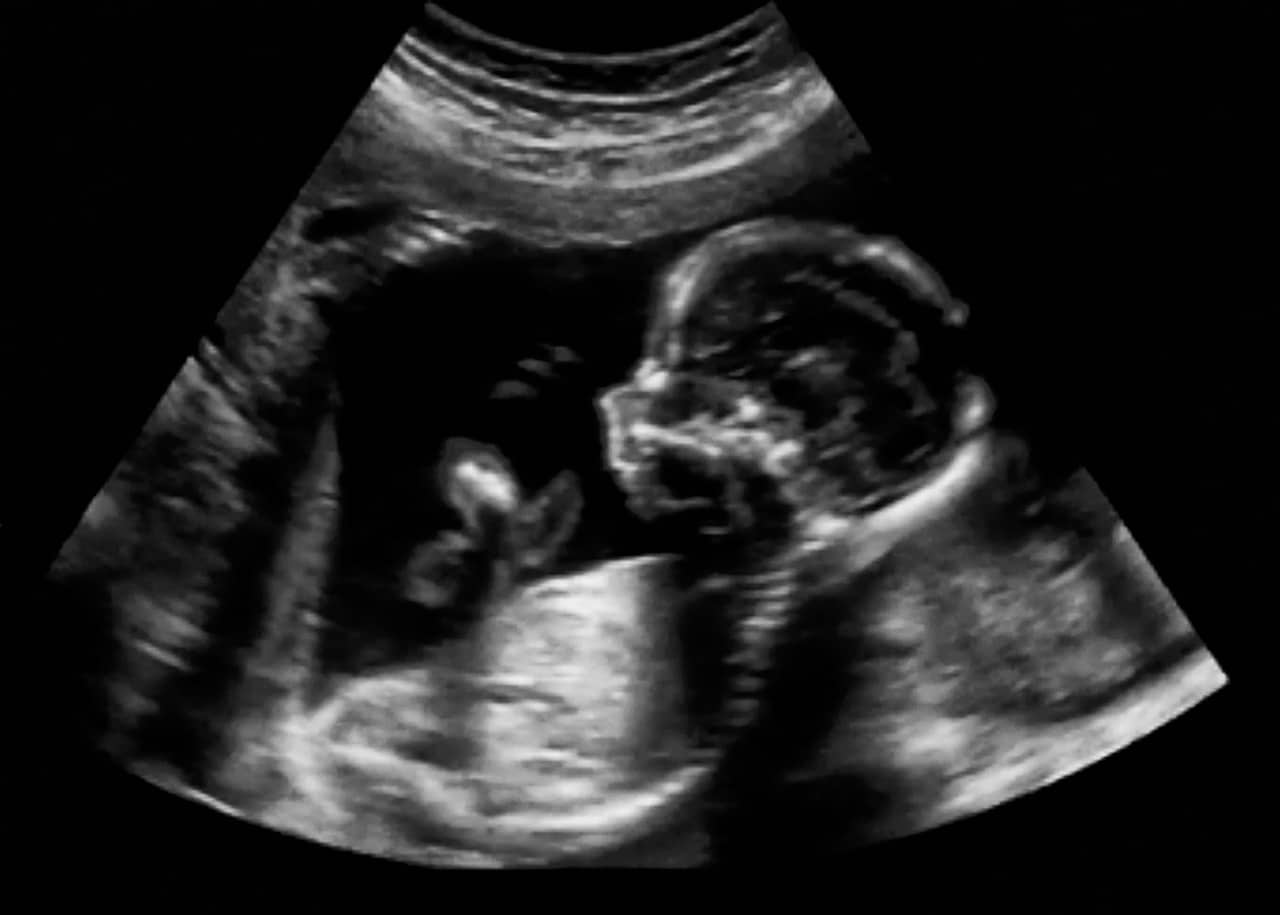

W ciąży badania USG są dużym wsparciem dla rodziców i lekarzy. Pozwalają zajrzeć do świata płodu, zobaczyć pierwsze ruchy i bicie serca, a przede wszystkim ocenić, czy rozwój maluszka przebiega prawidłowo. Dzisiejsza diagnostyka prenatalna daje dostęp do różnych typów USG ciąży – od podstawowych badań obrazowych po bardziej zaawansowane procedury. Każde z nich pełni istotną rolę na kolejnych etapach ciąży, pomagając monitorować rozwój dziecka i reagować na ewentualne nieprawidłowości.

To legendarne już badanie USG połówkowe, przeprowadzane ok. 20. tygodnia ciąży (między 18. a 22. tygodniem). Dlaczego jest tak ważne? To wtedy następuje szczegółowa ocena anatomii płodu. Jego głównym celem jest szczegółowa ocena anatomii płodu pod kątem występowania ewentualnych wad wrodzonych. To właśnie wtedy lekarz dokładnie sprawdza budowę narządów: serca, nerek, mózgu oraz kręgosłupa. Oprócz aspektów medycznych to również moment pełen emocji, bo podczas USG połówkowego rodzice zazwyczaj mogą poznać płeć dziecka.